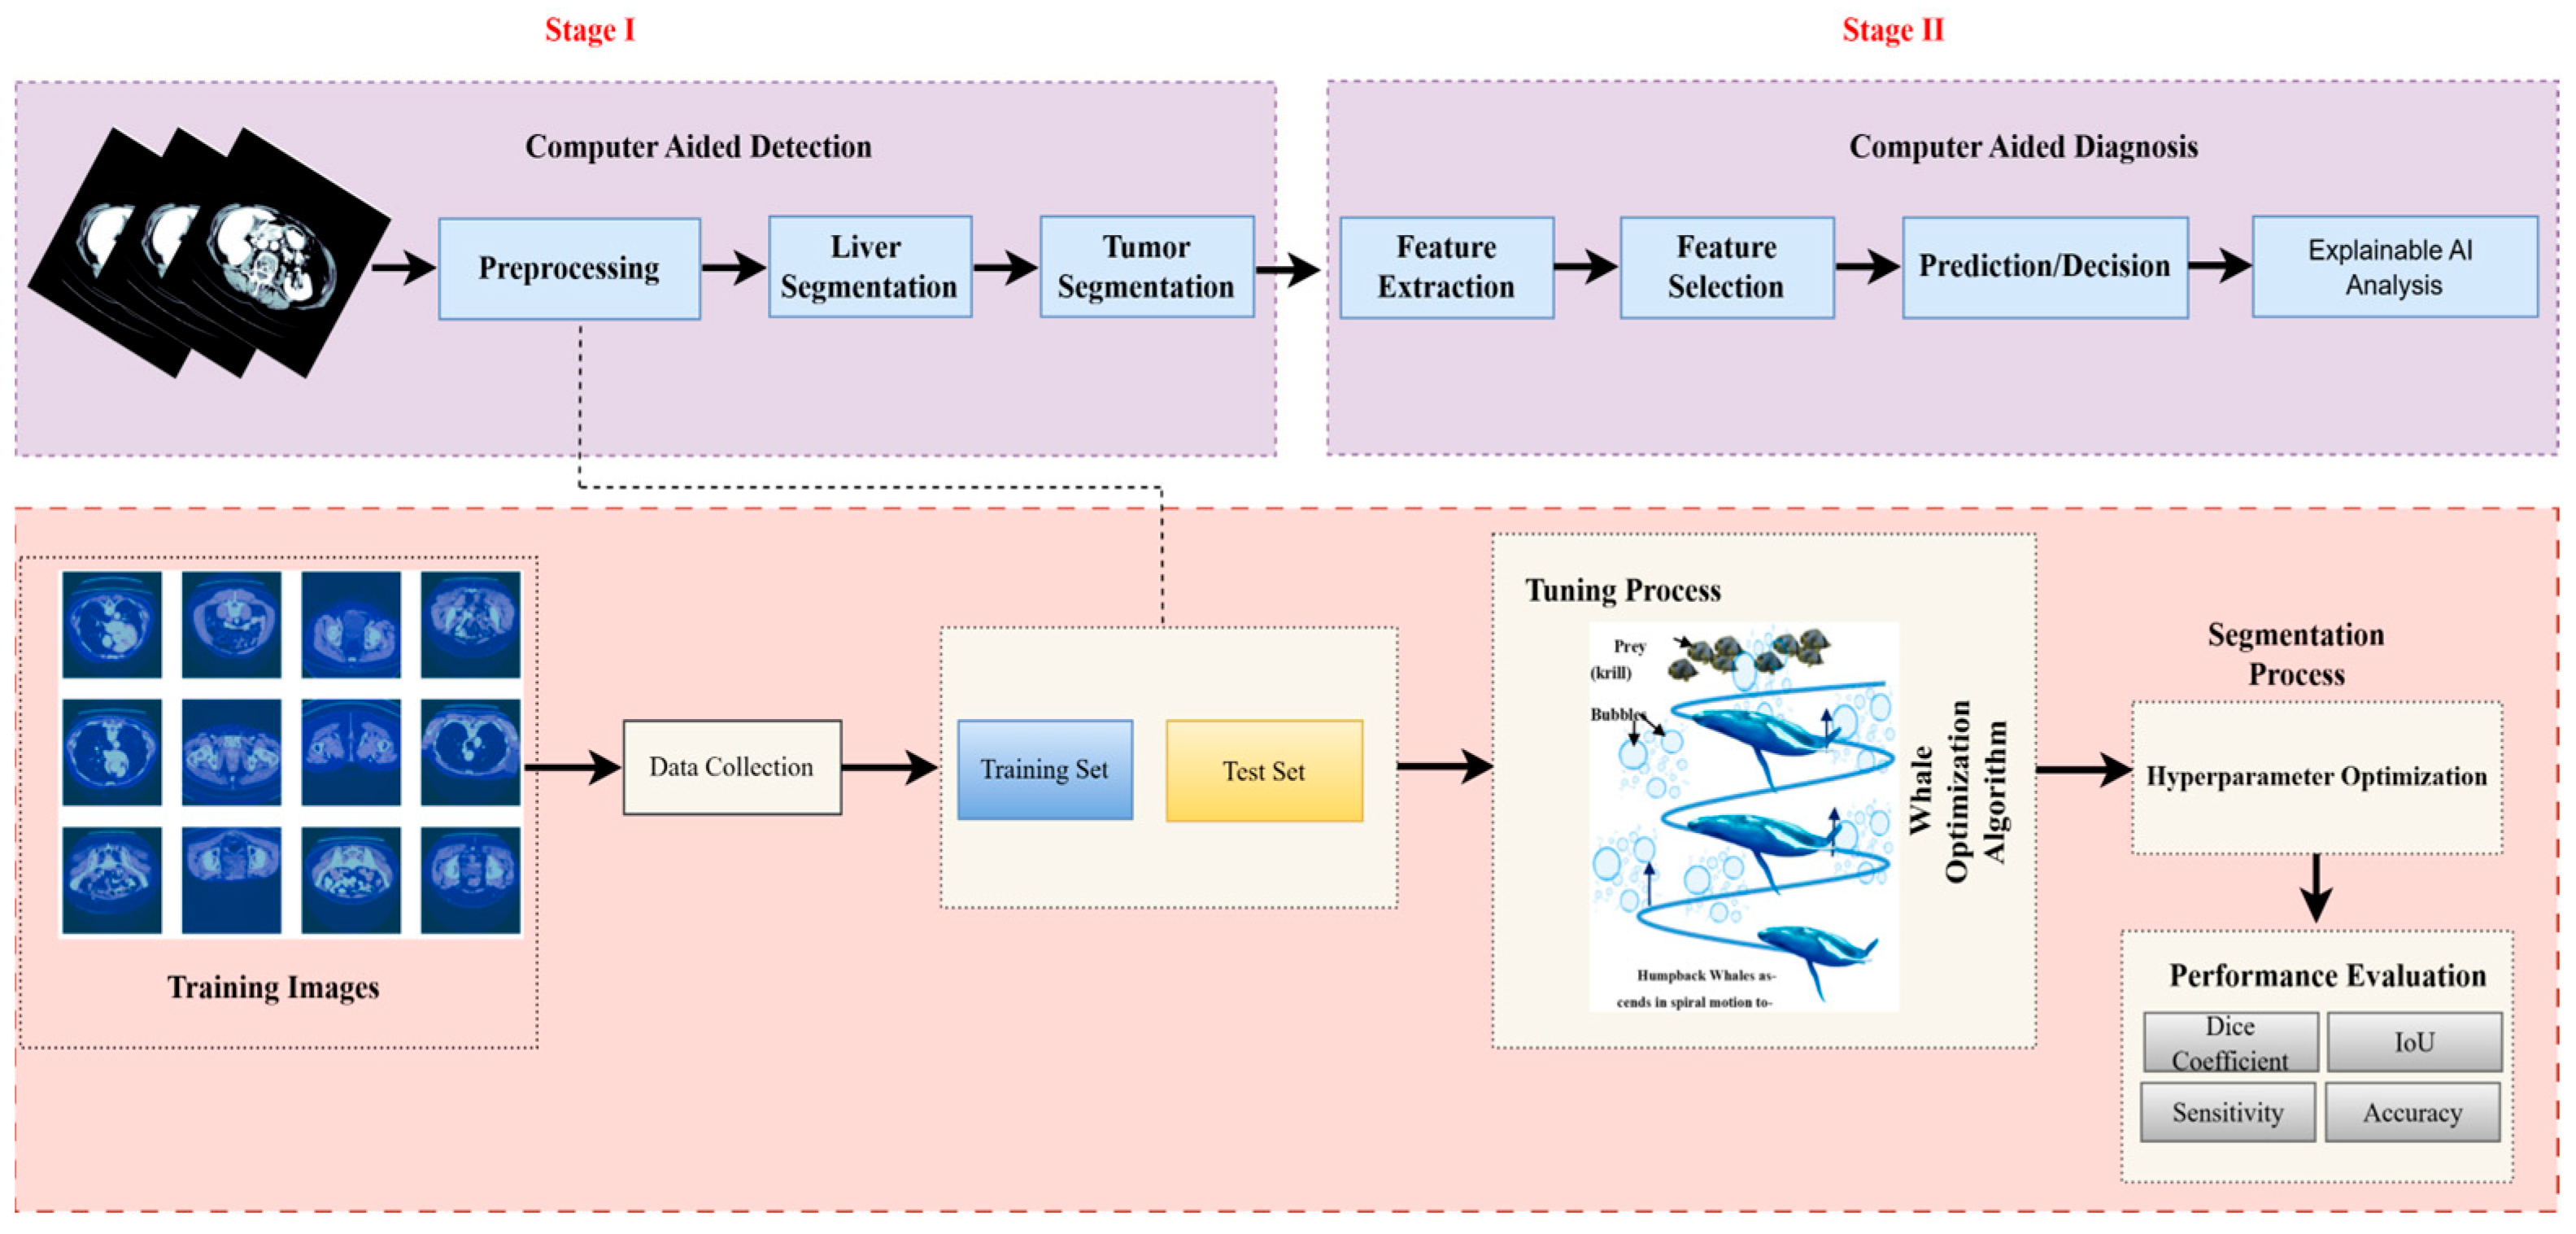

3. Methodology

3.1. Dataset Description

3.2. Dataset Preprocessing

3.3. Based Model Architecture

3.5. Proposed U-Net Segmentation with WOA

3.5.1. Hyperparameter Tuning with Whale Optimization Algorithm

3.7. Explainable AI (XAI)

3.8. Performance Measures

4. Experimental Results and Discussions

4.1. Implementation